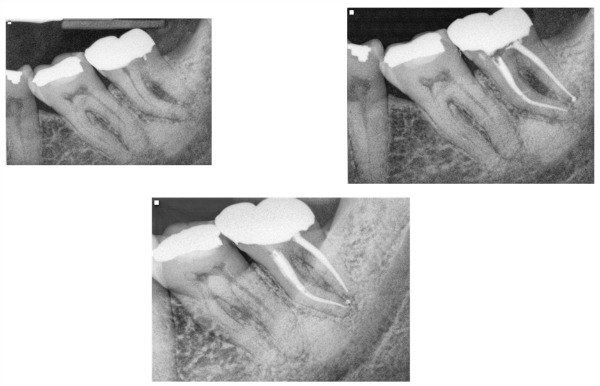

Fig.1 Here is a case of a furcal lesion treated by Dr. Michael Sherman. In the radiograph in the upper right you can see a small lateral canal on the mesial root communicating with the furcation. That lateral canal is filled with sealer and the 2 year recall shows excellent healing.

–lateral / furcal lesion caused by a primarily endodontic infection that creates the lateral and periodontal defect (figure 2,3)

Fig.2 Here is a case I treated about 1.5 years ago. The illustration shows the significant lateral and distal bone loss on the distal root of #18. The 8 month recall is on the bottom left side with red arrows showing excellent bone healing. This tooth went from a 2 mobility to rock solid before I had completed the case with 2 months of CaOH in the canals.

Fig. 3 This was a retreatment case by Dr. Sherman in which he medicated the canals over 3 appointments using CaOH. The upper left is the pre-operative x-ray. Upper right is the immediate post-operative x-ray and the lower x-ray is the 1 year recall. There has been significant bone fill into the furcation which will continue to improve over time.